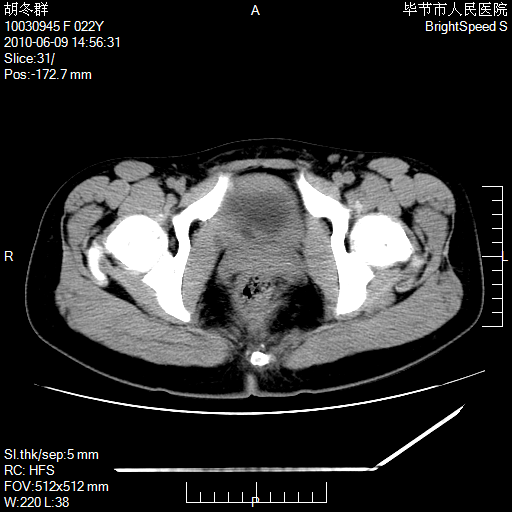

患者23岁,发现腹部包块3月。

左侧卵巢囊腺瘤或囊腺癌

盆腔内囊性占位性病变;考虑左侧卵巢囊腺瘤。

有分隔、壁薄,支持考虑左侧卵巢囊腺瘤。

左侧卵巢浆液性囊腺瘤。

支持考虑左侧卵巢囊腺瘤;宫腔积液。

有分隔、壁薄,支持考虑左侧卵巢囊腺瘤。排尿后,膀胱缩小,由于重力作用,肿块下移就到了膀胱位置,很好理解。